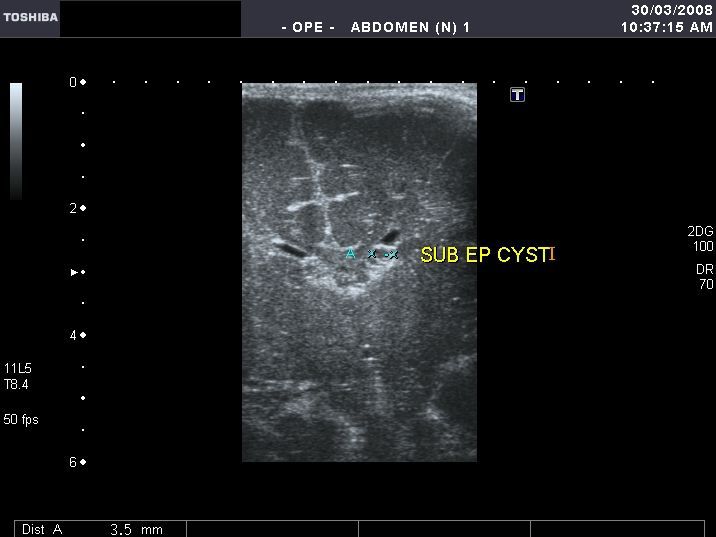

Another complication of subependymal hemorrhage- subependymal cysts

Sonography of the neonatal brain reveals a large subpendymal cyst of 3.5 mm. in the left caudato-thalamic groove. Sagittal section image also shows the true extent of the cyst. Such subpendymal cysts are a known complication of subependymal hemorrhage in neonates. Other causes of such cysts are intracranial infections. These are known to resolve spontaneously. The right side shows evidence of subependymal hemorrhage.